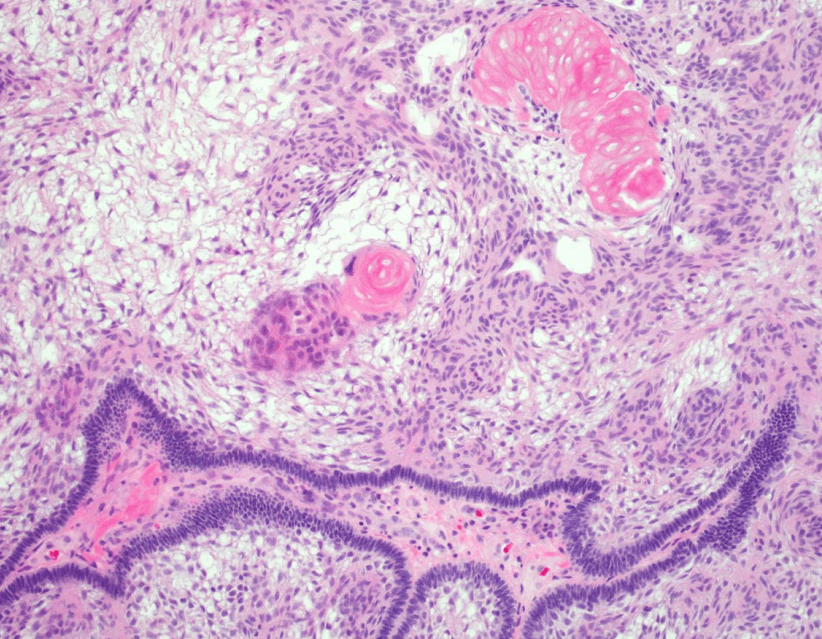

colon cancer